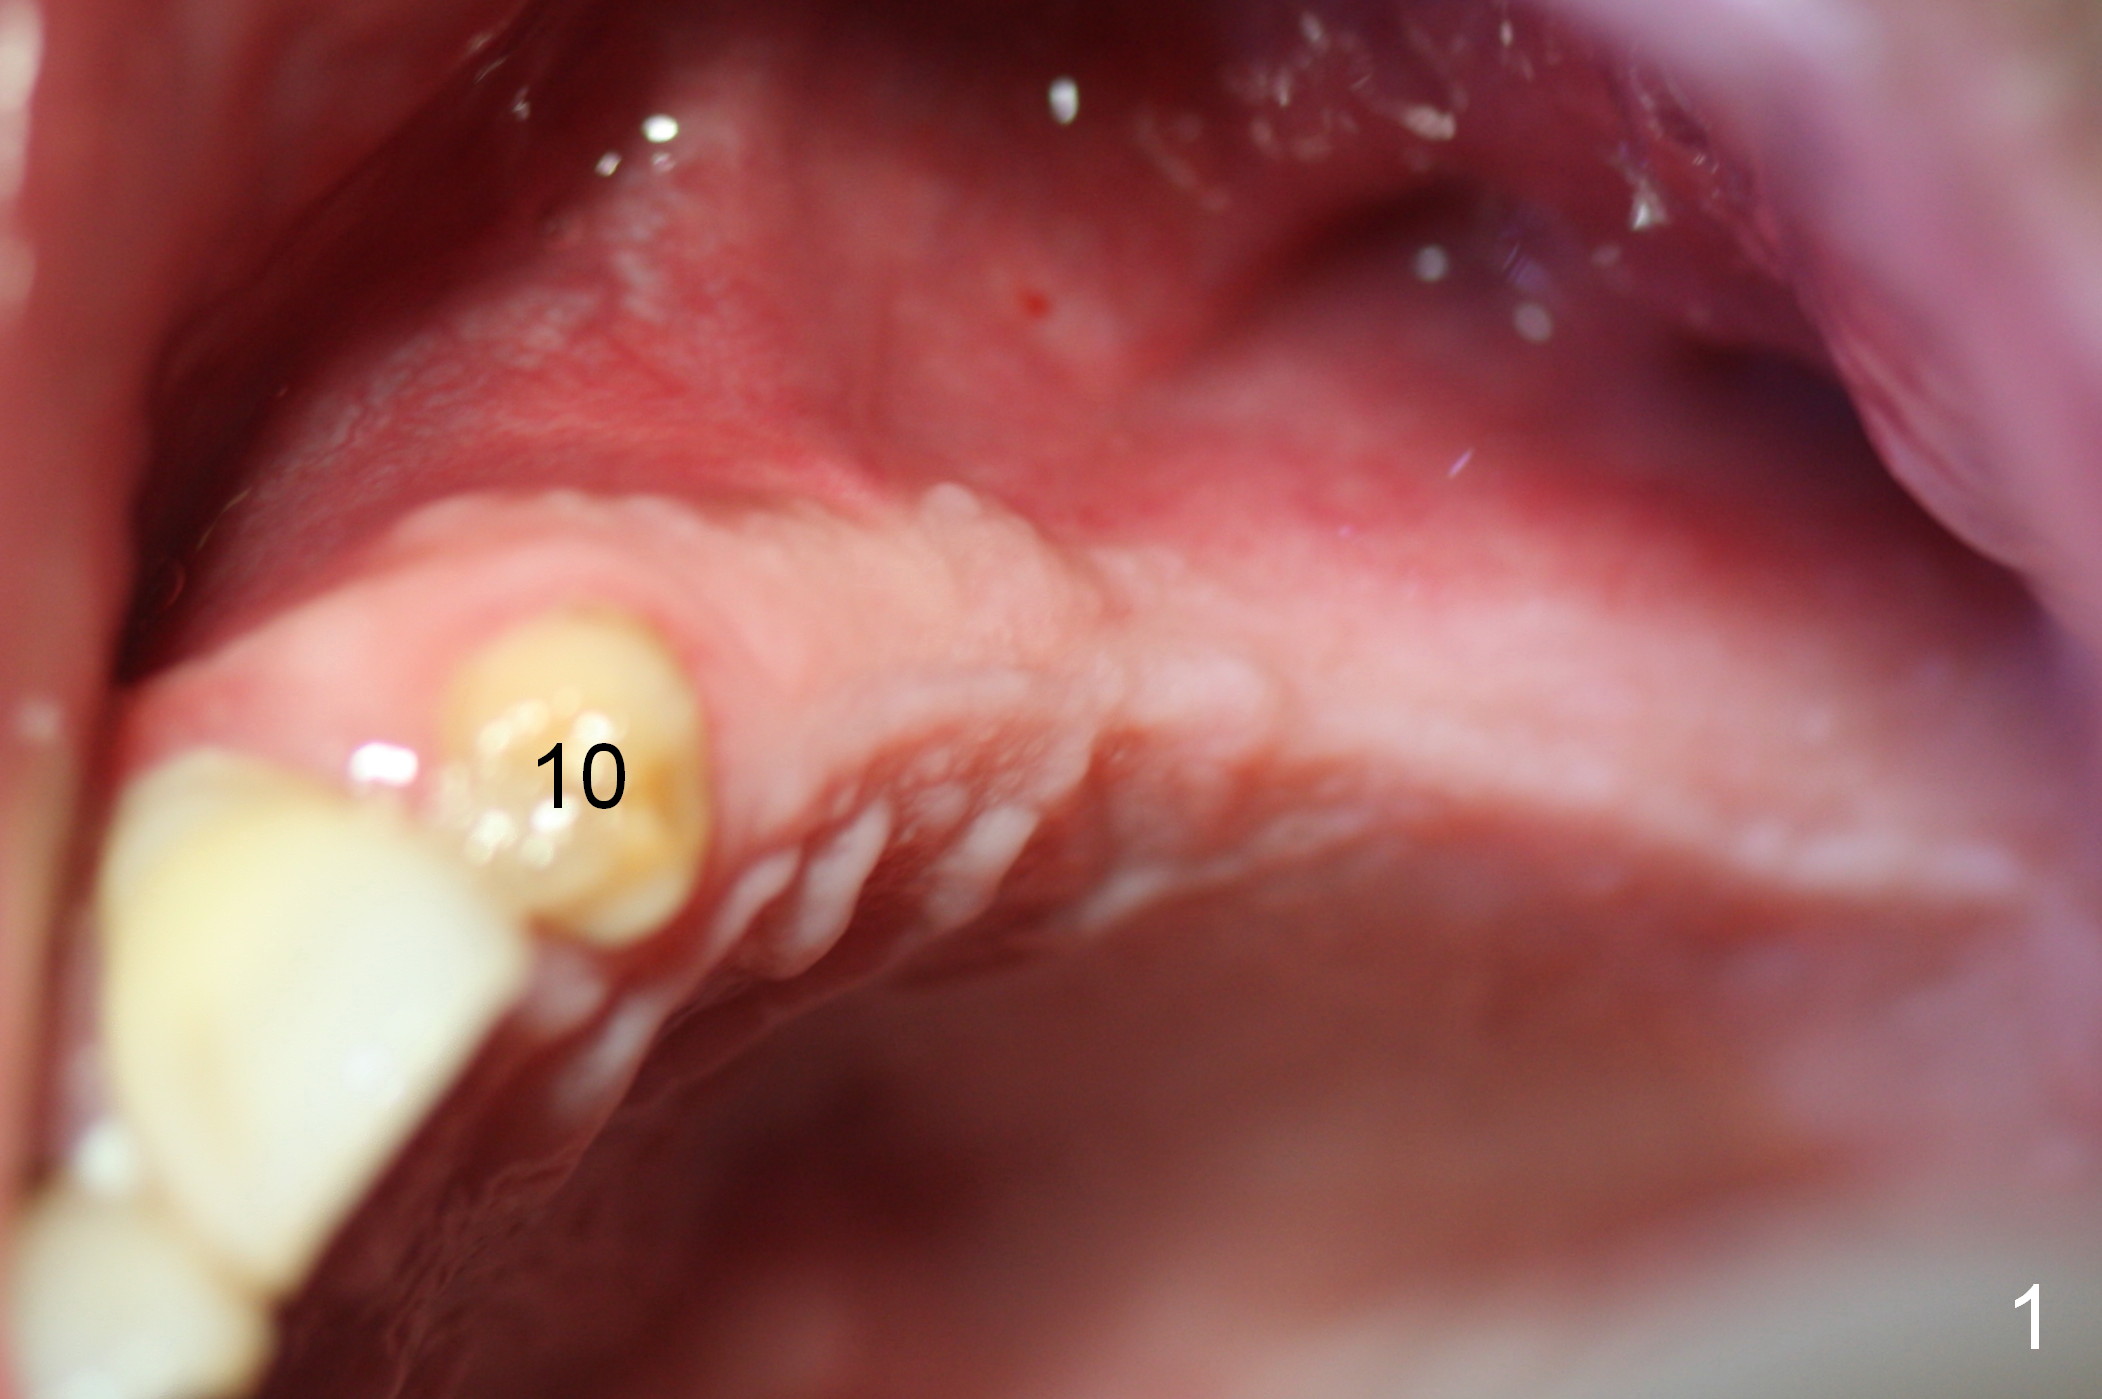

When the patient returns for implant placement (2nd visit after initial exam), he reveals that he is a dental phobic.  He requests placement of 4 implants in the upper left quadrant, instead of 2.  Narrow ridge is unexpected in the canine and premolar area (Fig.1).  Limited bone height at #13 (Fig.3 arrowheads: sinus floor) is found when initial drills are in place (Fig.2,3).  A 2-piece implant (4.5x17 mm tissue-level) is placed at #10 after extraction, while 1-piece implants are placed at 11 (3x17 mm (tissue-level, 15 °) and 12 and 13 (bone-level, 2.5x14, 12 mm, respectively; Fig.4,5).  In fact the 1 piece implant at #13 is not completely placed (Fig.5).  It is removed, the apical 3 threads are cut off (Fig.6 <, since a shorter implant was unavailable in the office) and the remaining implant is re-inserted.  The insertion torques of the 4 implants are ~ 60, ~ 35, < 35 and 15 Ncm, respectively.  After adjustment (Fig.7), immediate provisionals are fabricated at #10 and 11 (Fig.8, later splinted with composite), while perio dressing is applied around the implants at #12 and 13 and the provisionals at #10 and 11.  There is no nasal hemorrhage postop.  Although the perio dressing is loose 1 week postop (Fig.9), it is not removed.  When the upper lip fissure (Fig.9 <) heals, provisionals at #12 and 13 are planned to be splinted to the other two ones.  Two weeks postop, the upper lip fissure heals, the perio dressing dislodges and the implants at #12 and 13 are stable (Fig.10).  After abutment height adjustment, a splinted provisional is fabricated over these 2.5 mm 1-piece implants (Fig.11).